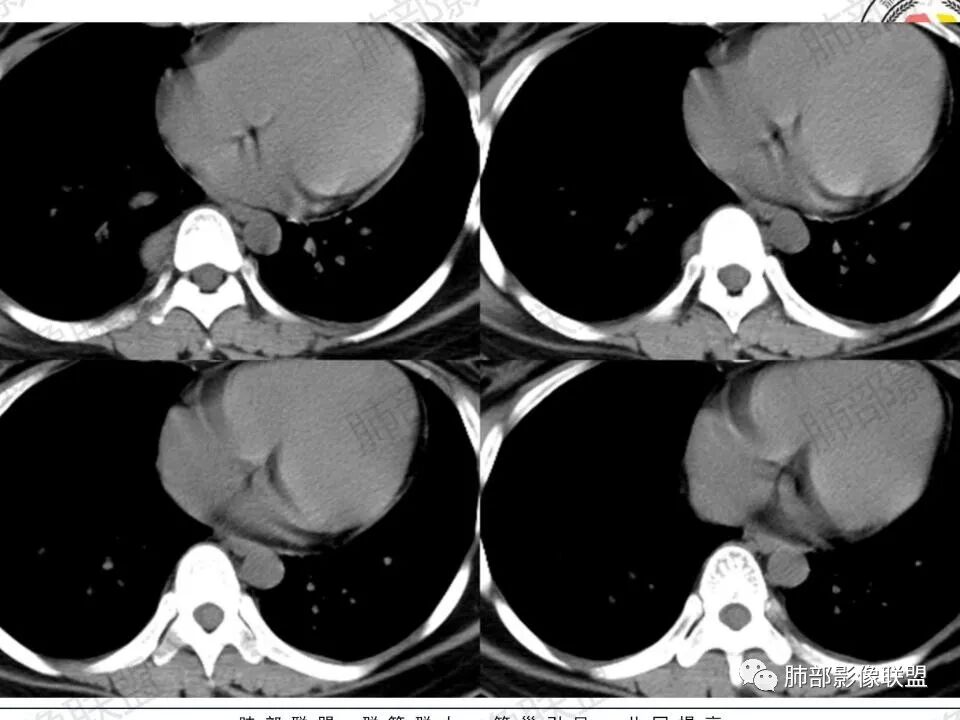

2.右后纵隔脊柱旁上下方向贴伏块影,“肾”形外观,边界清晰,密度不均,中央区域见脂肪密度影引向椎体前方,未见液性密度管腔影及钙化。

3.块影血供动脉来自肋间动脉,且由内后方侧入,其与下腔静脉之间未见回流通道。血管未见破坏,相邻组织未见侵入。

5.轻度渐进性强化。

(3)增強:

后纵隔神经节细胞瘤常动脉期无明显強化、或轻度间隔、包膜或瘤体强化,延迟期可进一步斑片、结节状轻度或中度强化,强化程度进行增加,呈渐进性延迟强化,但強化程度一般为轻度到中度强化,究其原因可能是神经节细胞瘤瘤体内含有大量黏液基质和胶原纤维,使得细胞外间隙扩大,阻碍了对比剂的灌注,从而延缓了对比剂的积累,因此其动脉期多无明显强化或仅有轻度强化,延迟期呈渐进性轻度强化是后纵隔神经节细胞瘤强化特征。大部分病灶有轻度-中度强化,部分病灶无强化,这还可能与瘤组织内部间质血管含量多少相关,无强化病例瘤组织内部主要由胶质纤维和节细胞组成,间质血管较少,因此强化较低,而强化程度较高的病理可见较多的扩张、充血的毛细血管,引起较多的对比剂积蓄,因此强化相对明显。因此,神经节细胞瘤极少出现瘤组织早期强化,而多呈延长渐进性强化,增强扫描神经节细胞瘤内细胞成分可增强,黏液基质不强化。